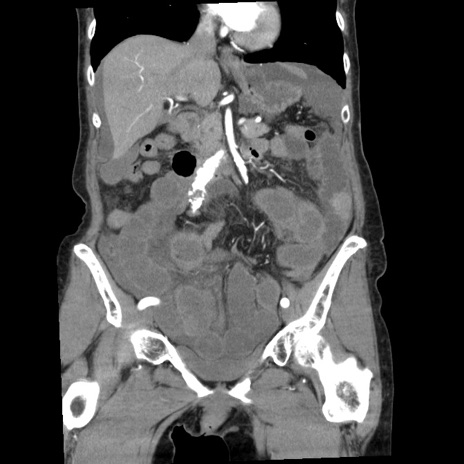

症例1(冠状断像)

【症例】80歳代女性

【主訴】腹痛

【現病歴】8時間前から腹痛あり来院。

【既往歴】糖尿病、脂質異常症、子宮体癌にて子宮全摘術

【身体所見】意識清明・会話良好だが腹痛で苦悶様、全腹部にわたって反跳痛と圧痛あり

【データ】WBC 13600、CRP 0.14、LDH 224、CK 90